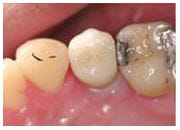

植入植體

治療後